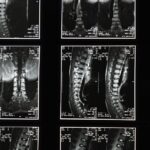

La décompression vertébrale est une méthode efficace visant à soulager les douleurs dorsales, en particulier celles liées aux affections discales. Après un traitement, il est crucial d’adopter des conseils post-traitement pour maximiser les bénéfices de cette thérapie. À Montréal, cette approche est vivement recommandée pour ceux qui cherchent une solution non invasive à leurs problèmes de dos. Les soins appropriés après une décompression neurovertébrale permettent non seulement de prolonger les effets positifs, mais aussi de réduire les risques de récidive et d’améliorer le confort au quotidien.

La décompression vertébrale est une méthode non invasive, efficace pour soulager les douleurs dorsales causées par diverses affections, comme les hernies discales. Après un traitement de décompression, il est essentiel de suivre certaines recommandations afin de maximiser les bénéfices de cette thérapie et de prévenir les récidives. Cet article présente des conseils pratiques pour optimiser votre réhabilitation post-traitement.

La décompression vertébrale est une méthode thérapeutique innovante qui permet de soulager efficacement les douleurs dorsales et cervicales. Après avoir bénéficié d’un traitement de décompression, il est essentiel d’adopter de bonnes pratiques pour maintenir les bienfaits et favoriser une récupération optimale. En effet, les conseils post-traitement jouent un rôle crucial dans le succès de cette thérapie.

La décompression neurovertébrale s’affirme comme une méthode efficace pour soulager les douleurs dorsales, et son succès ne s’arrête pas une fois le traitement terminé. Les conseils post-traitement sont cruciaux pour optimiser les bienfaits de la décompression, prolonger la récupération et éviter les récidives. En adoptant des gestes quotidiens adaptés, les patients peuvent réellement transformer leur qualité de vie.